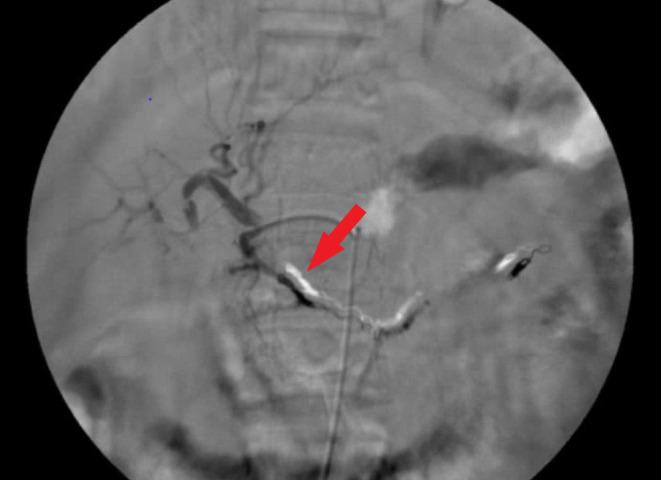

A 55-year-old woman with a history of coronary artery disease was referred to our hospital with abdominal pain as her primary complaint. Early works revealed anemia, a small amount of free peritoneal fluid, and a possible large aneurysm or pseudoaneurysm by the greater curvature of the stomach. She underwent emergency angiography that showed a large aneurism/pseudoaneurysm of the gastroepiploic artery. Successful embolization of the lesion was performed using the isolation technique. Perforation of a side branch of the gastroduodenal artery was observed on the immediate postembolization control angiography. Therefore, parent artery coiling was done immediately with good results. She was symptom-free and stable hemodynamically after the procedure, during the hospital course, and in the follow-ups.

一名有冠状动脉疾病史的55岁女性因腹痛为主诉被转诊至我院。早期检查发现贫血、少量腹腔游离液体,胃大弯处可能存在大动脉瘤或假性动脉瘤。她接受了急诊血管造影,显示胃网膜动脉有一个大动脉瘤/假性动脉瘤。采用隔离技术成功栓塞了该病变。栓塞后即刻控制血管造影观察到胃十二指肠动脉一分支穿孔。因此,立即对供血动脉进行了弹簧圈栓塞,效果良好。术后、住院期间及随访过程中她均无症状且血流动力学稳定。